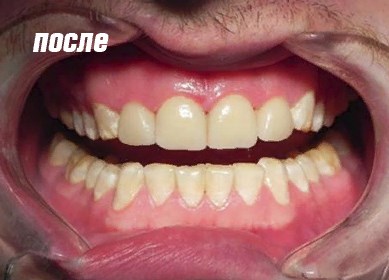

Результат восстановления зубов